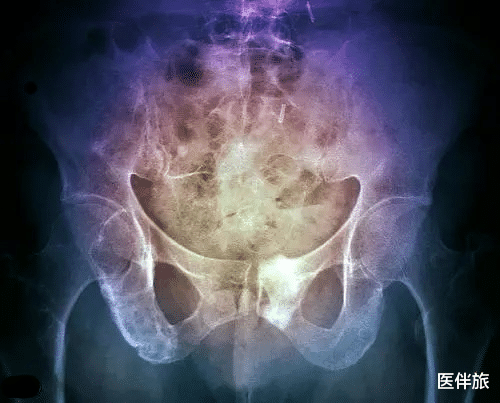

多发性骨髓瘤(MM)是由骨髓浆细胞分化而来的恶性浆细胞瘤,发病机制尚不清楚,临床表现为骨髓浆细胞异常增生伴有单克隆免疫球蛋白(M蛋白)过度生成。据WHO统计,2020年中国有超过2.1万例新病例和近1.62万例多发性骨髓瘤导致的死亡病例。令人惋惜的是,多发性骨髓瘤目前仍是一个无法治愈的疾病,任何治疗方法都无法将克隆性浆细胞消灭,复发是每一位患者都会经历的过程(1)。对于复发或难治性多发性骨髓瘤,塞利尼索以其全新的机制,成为多发性骨髓瘤患者安全有效的新选择!